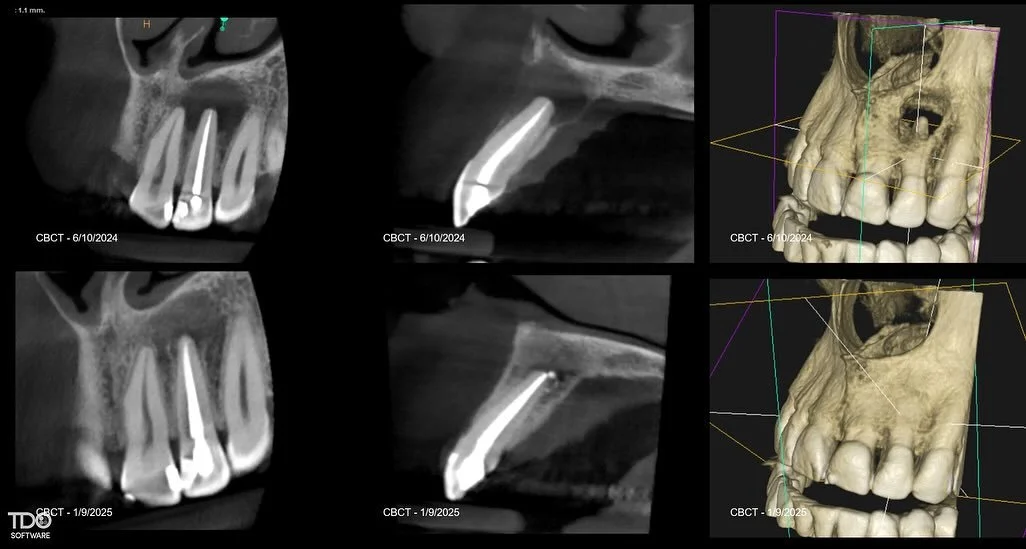

I am a board-certified endodontist with advanced specialty training and an academic interest in diagnostic reasoning, retreatment, and microsurgical endodontics. My work emphasizes CBCT-guided decision-making, interdisciplinary collaboration, and evidence-based care in complex clinical scenarios.

Board certification in endodontics represents an advanced level of professional achievement beyond specialty training. It is a voluntary, multi-year process that requires successful completion of a comprehensive written examination and rigorous peer review of complex clinical cases, evaluating diagnostic judgment, technical execution, and long-term outcomes. Less than 25% of practicing endodontists achieve board certification, reflecting a commitment to clinical excellence, continual self-assessment, and the highest standards of the specialty.